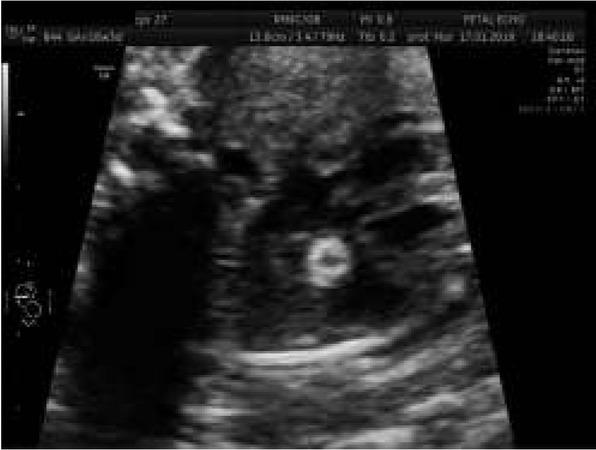

Abnormal view of the fetal heart at 29th week of gestation with pericardial effusion of 5 mm – one of the signs of congestive heart failure and fibroelastosis of enlarged left ventricle.Ryc. 4. W 29 tyg. nieprawidłowy obraz serca płodu z cechami niewydolności krążenia – wysięk w osierdziu 5 mm oraz fibroelastoza powiększonej lewej komory serca.